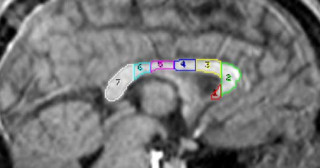

チンパンジーとヒトの脳梁の発達を比較 -ヒト特有の言語、数概念に関わる神経の成熟は乳児期が鍵-